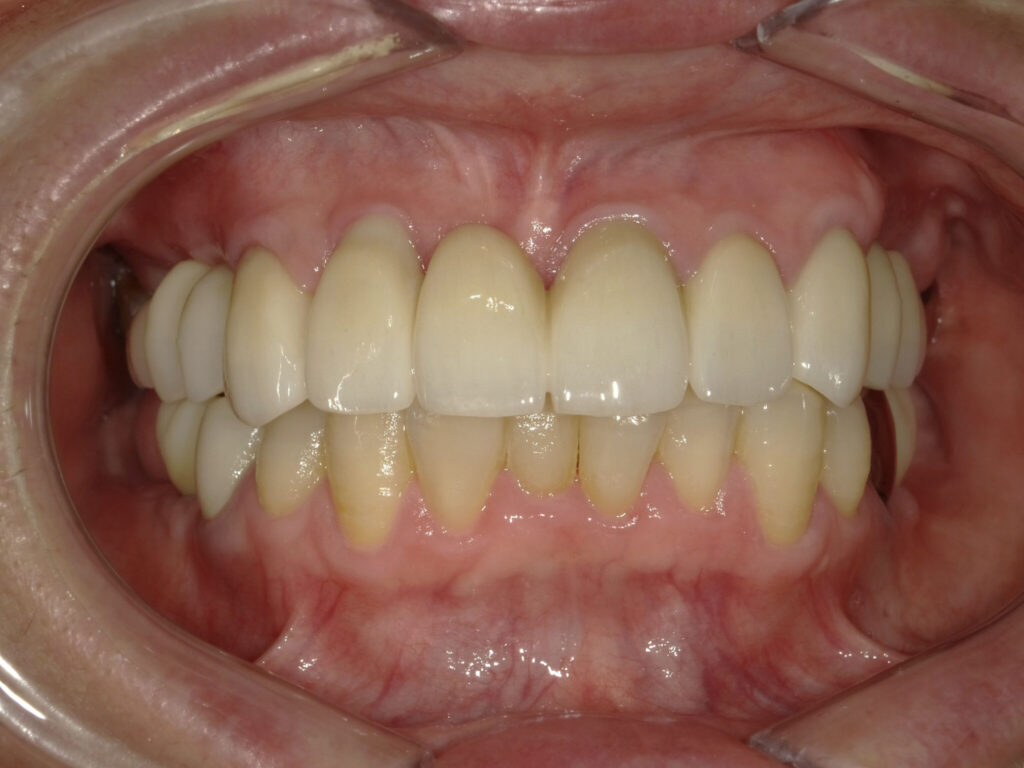

インプラント埋入(左下5・6,右下5・6,左上4・6) サイナスリフト(左上4・6) ジルコニアBr(右上6−左上3) E …続きを見る